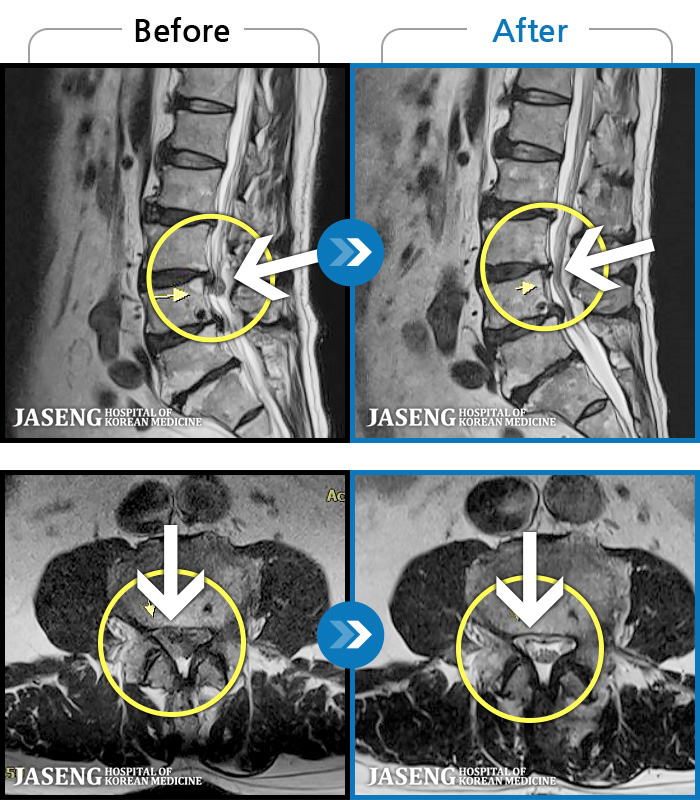

MRI ġ

1,299 MRI ũ ʸ Ȯϼ.